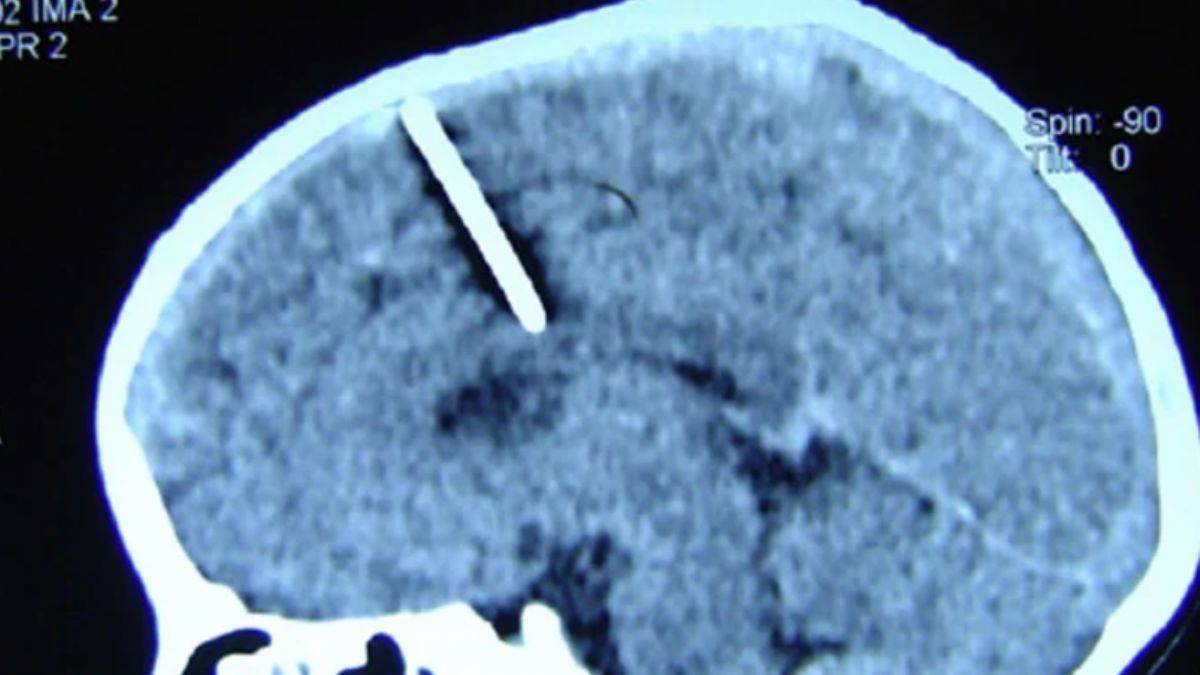

80 yıl boyunca beynine saplı iğneyle yaşadı

Rusya'nın doğusunda yaşayan yaşlı bir kadının, tüm hayatını beyninde 3 cm uzunluğunda bir iğne ile yaşadığı, doktorların tomografi çekmesiyle ortaya çıktı.

Doktorlar, 80 yaşındaki kadının, ebeveynleri tarafından gerçekleştirilen başarısız bir çocuk düşürme girişimi nedeniyle bu durumda olduğunu düşünüyor.

Durumunun kötüleşmesinden korkulduğu için iğnenin çıkarılmamasına karar verildi.

Rusya'nın Sakhalin bölgesindeki yerel sağlık departmanı, "Kıtlık yıllarında bu tür vakalar nadir değildi. Anne ve babası muhtemelen, İkinci Dünya Savaşı sırasında çocuklarını ölüme göndermeye karar vermişti. Doğduğundan beri 3 cm uzunluğundaki iğneyle yaşıyor." dedi.

Yerel sağlık departmanı, "İğne sol parietal lobuna girdi, ancak amaçlanan etkiyi yaratmadı; kız hayatta kaldı" diyerek, hastanın yaralanma nedeniyle baş ağrısından hiçbir zaman şikayet etmediğini ve herhangi bir tehlike altında olmadığını da sözlerine ekledi.

Durumunun ilgili hekim tarafından takip edildiği belirtildi.